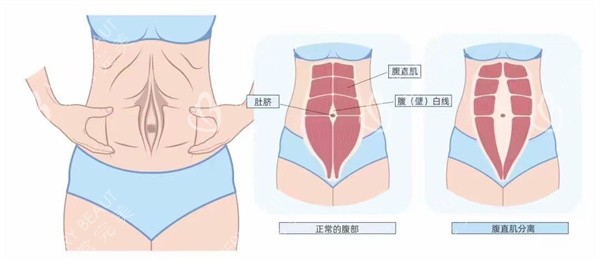

在上海进行腹直肌修复手术的总费用大约在18000-55000元左右,具体价格因手术方式、医生资质和术后护理方案而异。腹直肌修复手术是针对产后腹直肌分离或腹部肌肉松弛的正规医疗解决方案,下面我们将分类详细列出上海地区腹直肌修复手术的各项费用明细。

需要特别说明的是,腹直肌修复手术属于个性化定制医疗服务,每位患者的具体情况不同,建议先做评估后再确定较终治疗方案。选择正规医疗机构和经验充足的正规医生是确保手术健康和结果的重要确保。术后严格遵循医嘱进行改善训练同样至关重要。